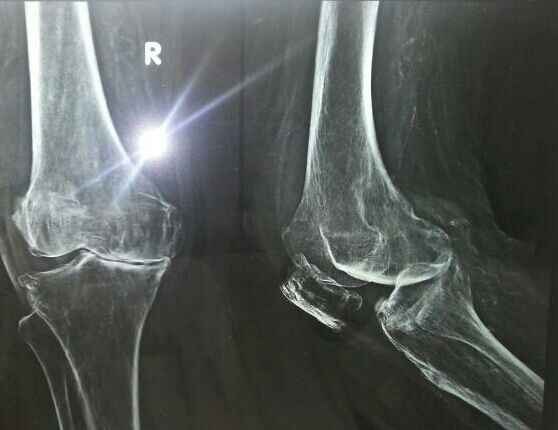

Knee Replacement

"Shailesh bhai, had Severe Arthritis in knee, underwent a total knee replacement surgery performed by Dr. Chandresh Sharma at Lifeline

Shailesh